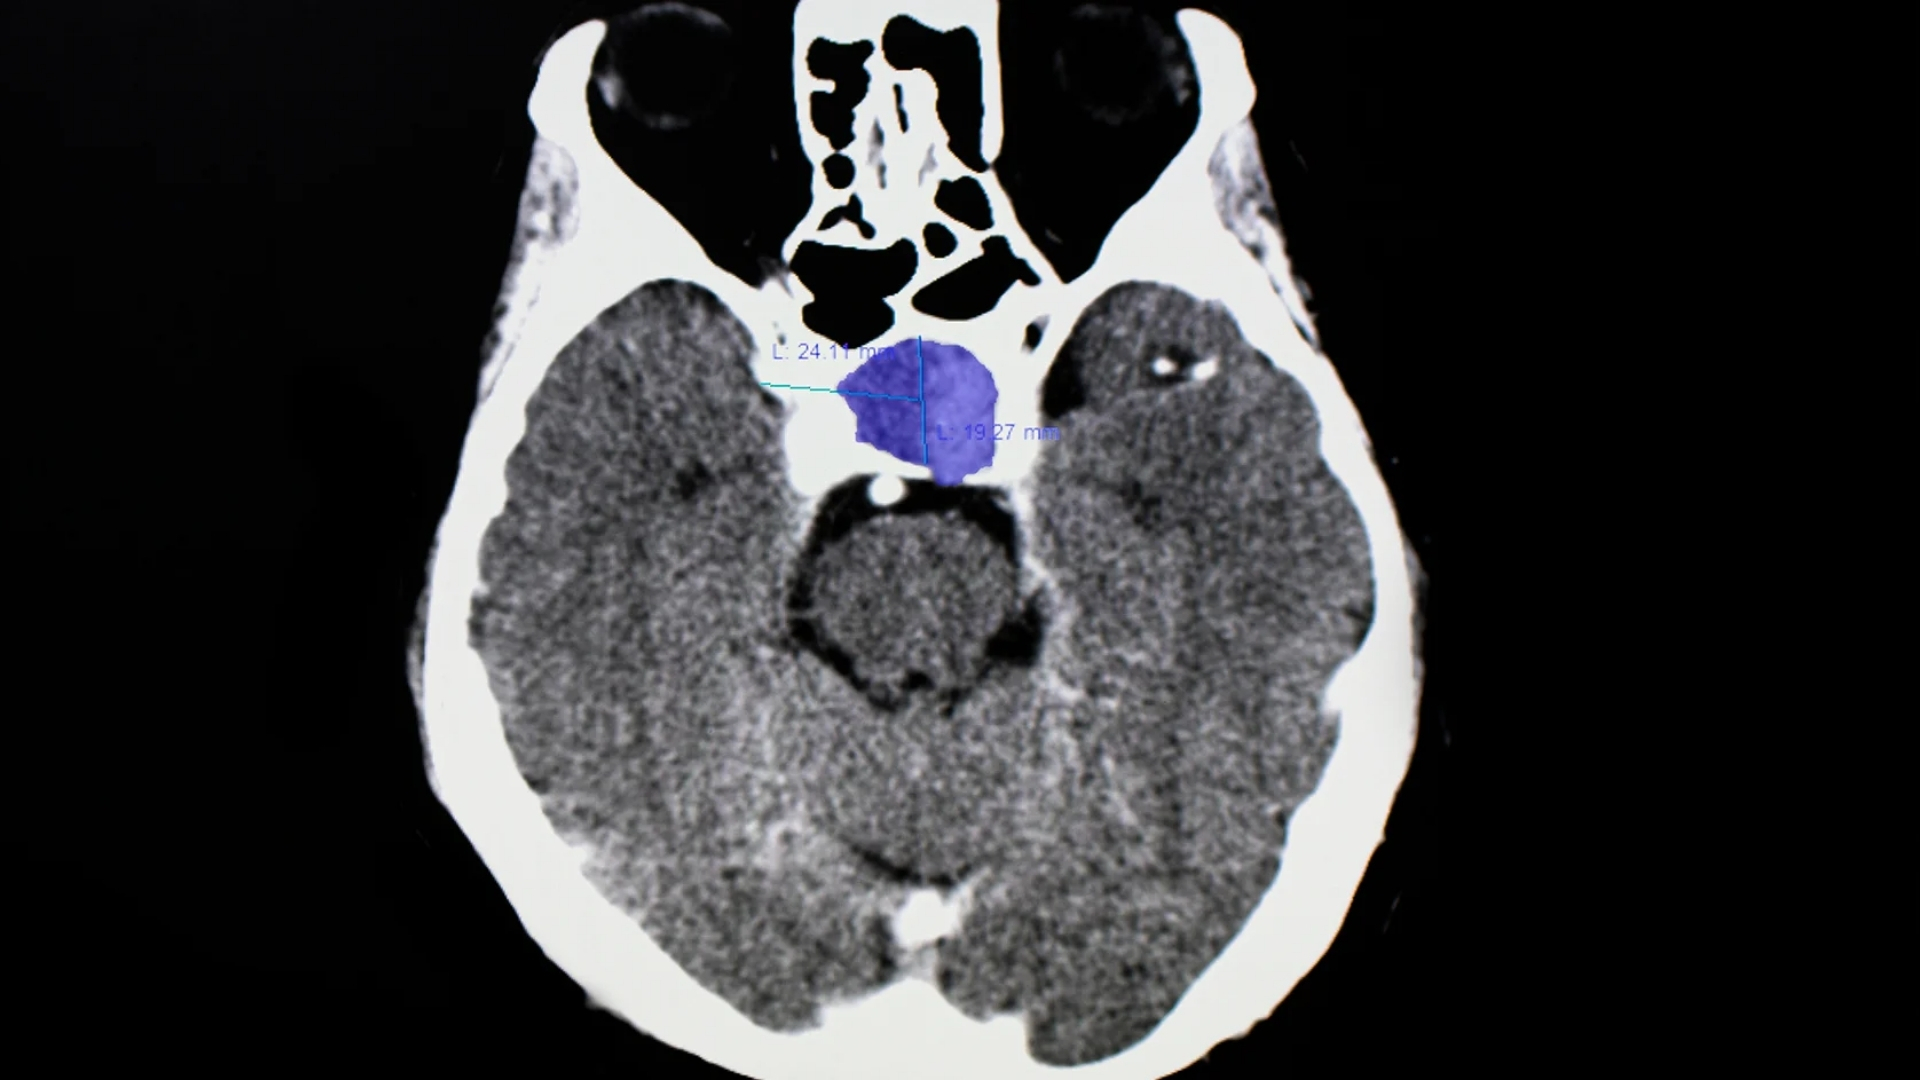

先進診斷技術

傳統的造影技術如**MRI(磁力共振掃描)**是檢測**垂體瘤(垂體腺瘤)**的基礎,因為它們在建立軟組織(如垂體)的詳細影像方面表現卓越。**MRI** 仍然是檢視垂體腺瘤、界定其大小以及評估其是否影響周圍結構的黃金標準。

此外,**PET-CT (Positron Emission Tomography-Computed Tomography) **也可能用於某些病例。這有助於顯示腫瘤的新陳代謝活動,提供額外的洞察力。這對於區分垂體腺瘤和其他腦部病變尤其有用。